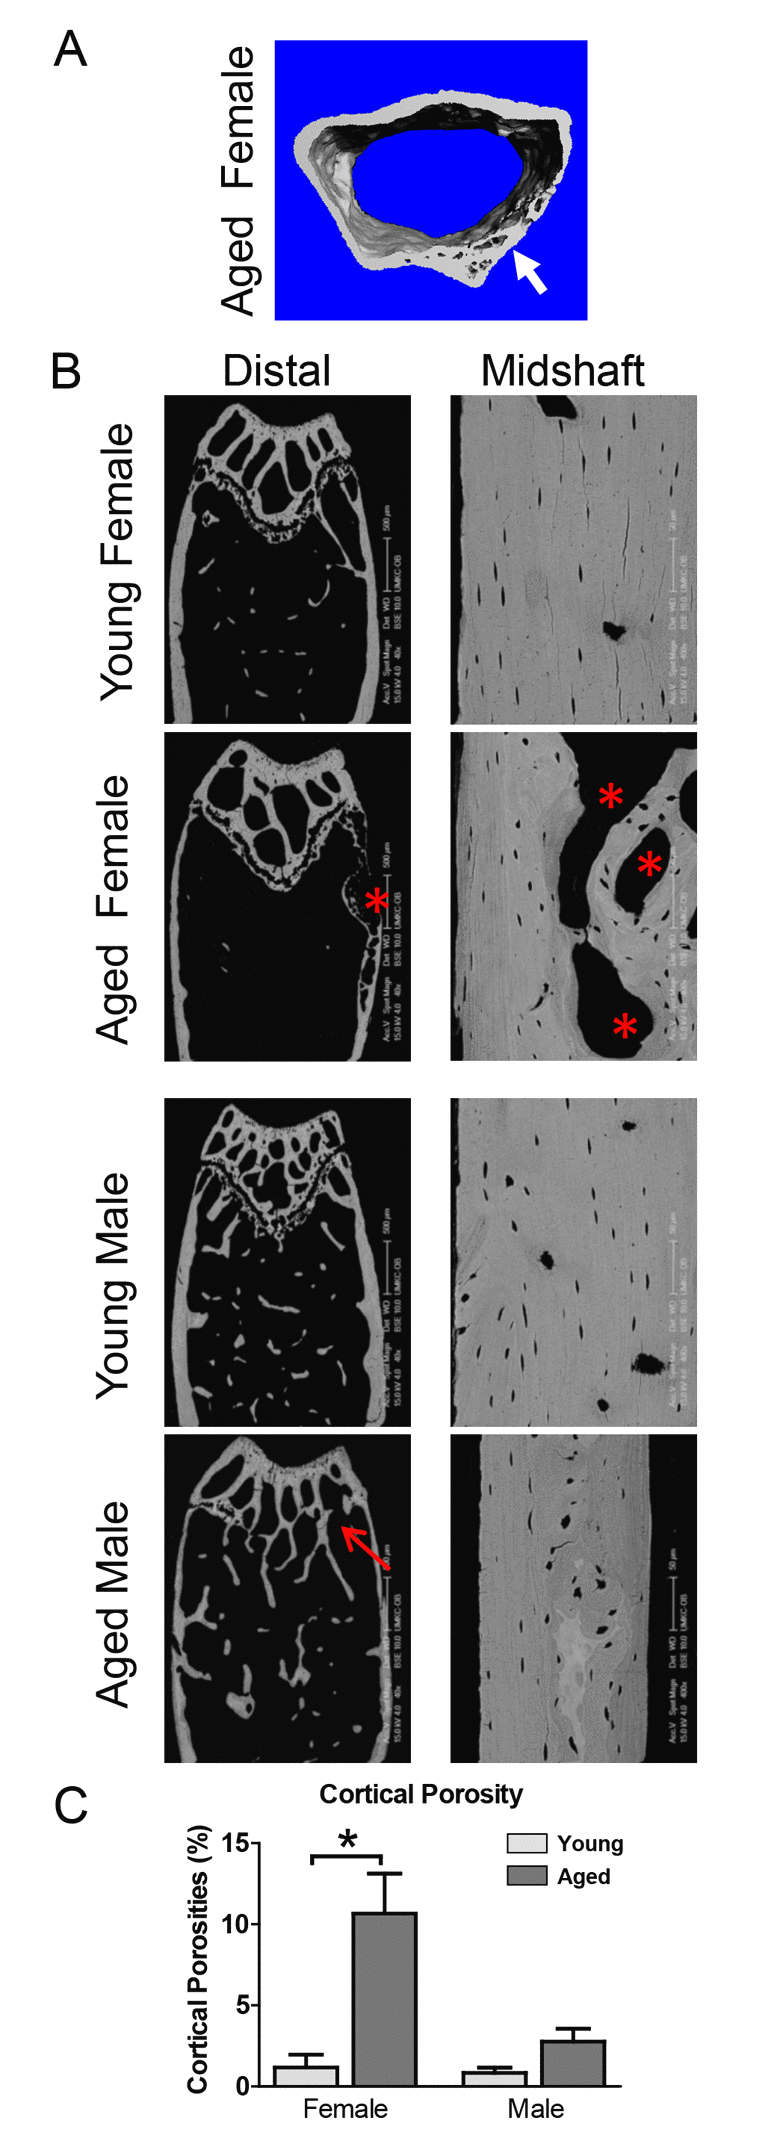

Cortical porosities were observed in the femurs in several of the aged mice, particularly in females at the distal end (see Fig. 2A arrow and 2B asterisks). Therefore, an additional cortical analysis was performed on the distal femur. This showed that the distal cortical BV/TV was significantly decreased by 6.3% in females but not males (Fig. 1H), consistent with increased cortical porosities. Females but not males showed a significant 19% decrease in distal cortical bone area (Fig. 1I) and 20% increase in distal cortical bone perimeter (Fig. 1J). The reduced cortical thickness was more pronounced in the distal region than the midshaft, with a significant 36% reduction in females and a 19% reduction in males (Fig. 1K). Distal cortical bone parameters were not statistically significant between genders except for distal cortical bone thickness, which was significantly lower in males vs. females at 5mo (Fig. 1K).

Figure 2. Aging is associated with cortical porosities, regional variation in mineral density and growth plate closure. (A) microCT reconstruction of distal femur cortical bone in an aged female showing cortical porosity (arrow). (B) BSEM image of the distal femur (Bar = 500μm) and midshaft cortical bone (Bar = 50μm) in young and aged C57BL/6 mice. Arrow indicates growth plate closure in the aged male and * indicates cortical porosities. (C) Quantitation of cortical porosity from n=5 animals showing a significant increase in cortical porosity in female C57BL/6 mice with age.

Backscattered SEM (BSEM) shows cortical porosities in aged mice and closure of the growth plate in aged males

BSEM confirmed reduced cortical thickness and expansion of cortical diameter in aged compared to young mice and showed cortical porosities in several of the aged mice, particularly females (Fig. 2B, asterisks). This was more prevalent at the distal end of the femur. In all male mice, the growth plate was either completely or partially closed (Fig. 2B, arrow). BSEM also showed greater regional variability in bone density in aged mice, indicated by variation in greyscale intensity of the cortical bone (Fig. 2B). Quantitation of the cortical porosities revealed a significant increase in porosity in females but not males with age (Fig. 2C).